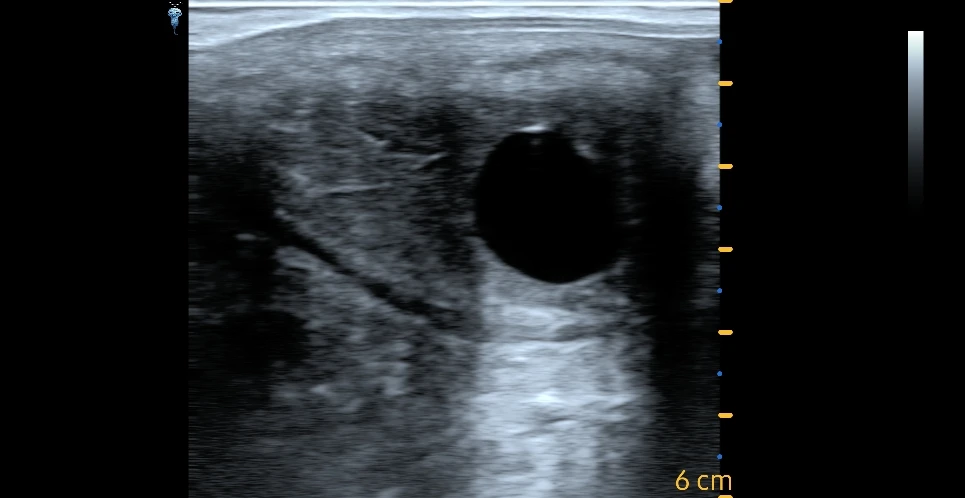

00:23#Sonoscape Ultrasound Scanner

00:04Ultrasound Scanner mindray

01:49Color Doppler Machine

00:44Color Doppler Machine

00:23#Sonoscape X3 ultrasound machine

02:22Color Doppler Machine

02:48Color Doppler Machine